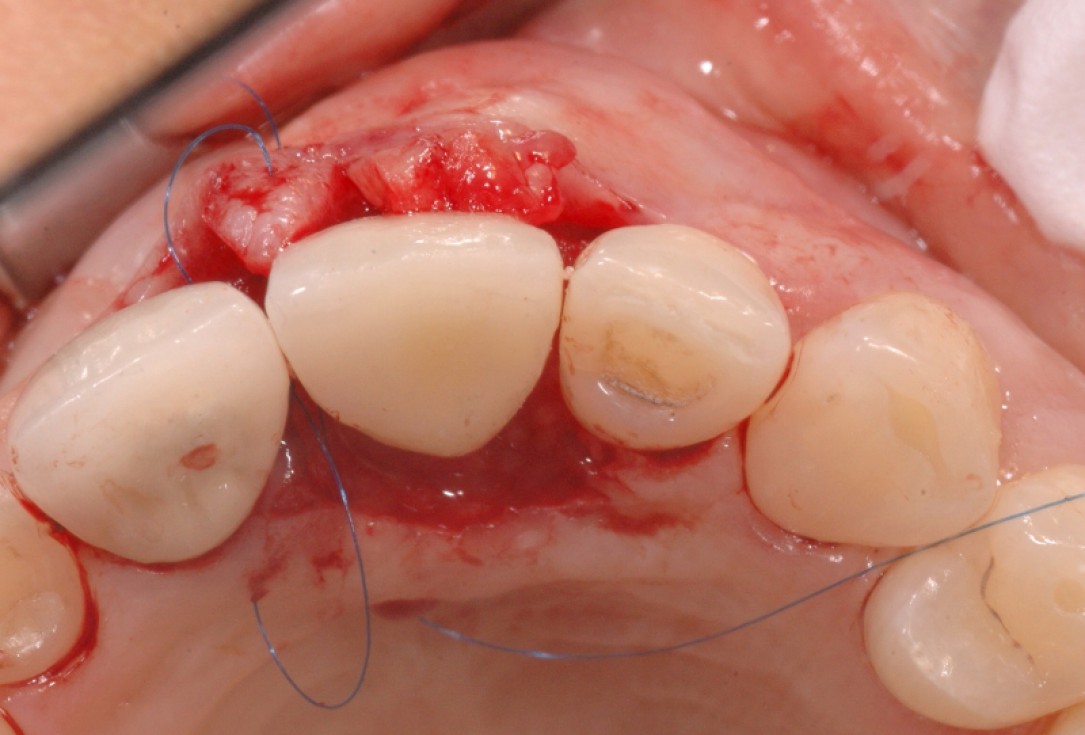

5/18 - Situation after implantation showing a buccal defectGBR together with soft tissue augmentation with mucoderm® and maxresorb® - Dr. S. Scherg